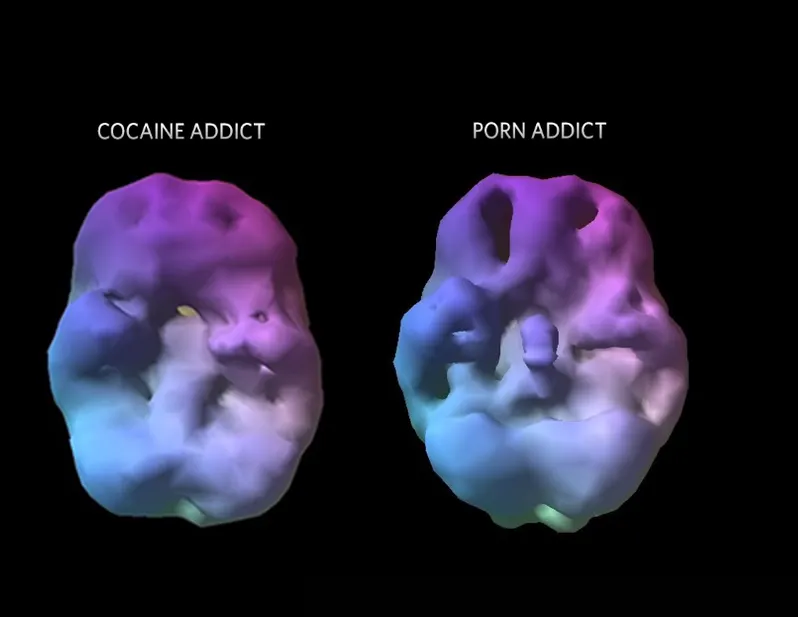

Còn đây là ảnh não bộ con người khi xem “phim con lợn”. Như bạn thấy đấy, não bị thoái hoá giống như khi bạn đang dùng “nàng tiên nâu”.

Đối với nhiều người, phim người lớn là một công cụ vô hại để khám phá và giáo dục giới tính. Nhưng một nghiên cứu năm 2015 cho thấy nam giới thường xuyên xem chúng bị giảm chất xám ở các vùng não chịu trách nhiệm về động lực và khả năng ra quyết định. Những người xem nhiều cũng cho thấy khả năng phản ứng với các kích thích tình dục nói chung giảm sút.

Não thay đổi do xem phim người lớn nhiều

Phim con lợn mang lại những liều dopamine mạnh mẽ vượt xa những “phần thưởng” bình thường như thức ăn hay giao tiếp xã hội. Theo thời gian, hiệu ứng siêu kích thích này gây ra hai thay đổi lớn:

- Các trung tâm kiểm soát ở não bộ thu hẹp: Chất xám và kết nối thần kinh ở các khu vực như thuỳ trán não – nơi điều khiển khả năng tự chủ và ra quyết định – dần co lại.

- Làm rối loạn “cơ chế giải thưởng”: Các mạch dopamine trong trung tâm khoái cảm của não bị quá tải, đòi hỏi kích thích cực đoan hơn nữa để đạt được cảm giác “phê” tương tự.